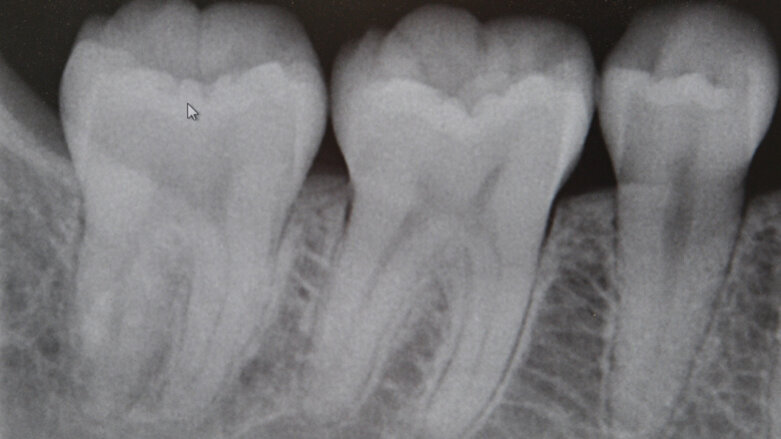

Nun haben Forscher der McMaster University jedoch einen Weg gefunden, einen Mangel an Vitamin D anhand der Zähne abzulesen – ohne sie dabei aufspalten zu müssen. Möglich wird dies, weil ein eindeutiger Zusammenhang zwischen dem Vorhandensein des Vitamins und der Pulpaform ausgemacht wurde. Der Vorteil: Ein unkompliziertes Ablesen mithilfe von Röntgenaufnahmen wird realisierbar.

Zeigt die Zahnpulpa eine gerade Form, die einem Stuhl ähnelt, kann man von einem starken Vitamin-Mangel ausgehen. Ein geschwungener Verlauf mit „Hörnern“ sagt hingegen, dass alles in Ordnung ist.